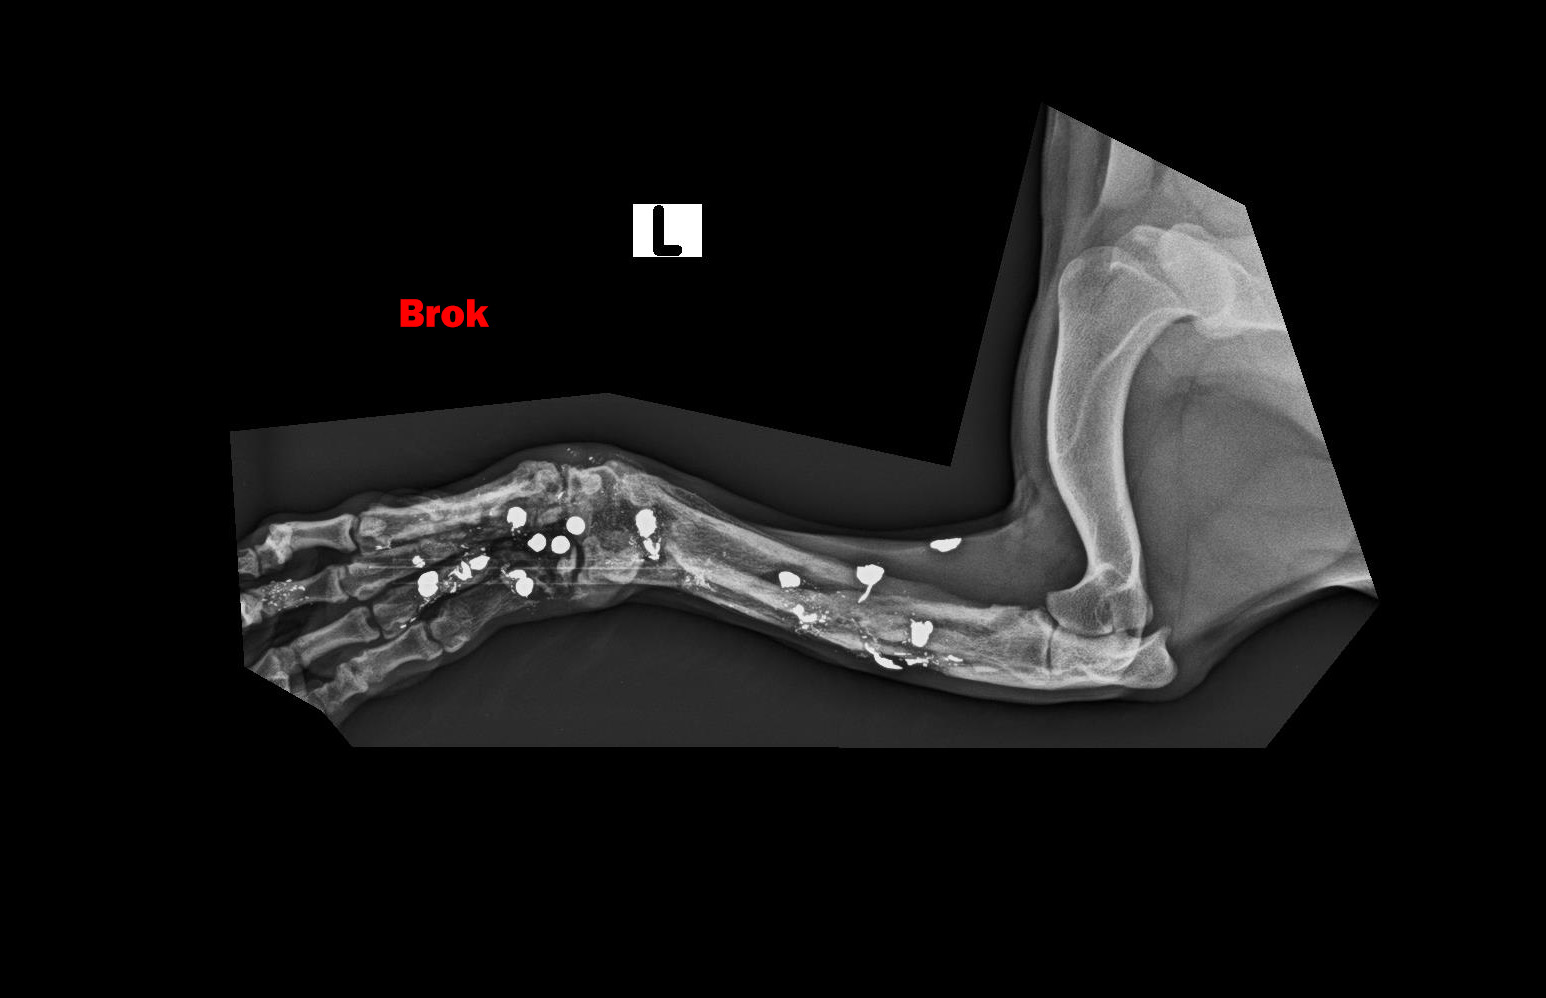

BROK - dostal meno Brok, keďže sa stal živým terčom a má vo svojom malom telíčku nespočetné množstvo brokov. Labka je vykrivená preto, že sa mu v dôsledku streľby dolámali kosti...

Image removed.BROK - dostal meno Brok, keďže sa stal živým terčom a má vo svojom malom telíčku nespočetné množstvo brokov. Jeho brata sme odchytili pár mesiacov pred ním, keď do neho deti hádzali petardy. On z toho vyviazol bez problémov, ale žiaľ Brok to šťastie už nemal. Jeho celá nožička je zdeformovaná, dostieľaná, dolámaná. On nenatrafil na deti, ale na dospelého, zjavne psychicky narušeného človeka, ktorý mu neskutočne ublížil. Odpusťte mi, keď do prosby vnesiem aj emócie, ale pri pohľade na neho sa topím v slzách. Brok je jeden z najláskavejších psíkov akého sme kedy mali. Miluje ľudí, objíma ich aj tou boľavou nožičkou. Rozdáva pusinky každému. Má celý život pred sebou. Tak rád by bezstarostne behal a naháňal sa, ale potkne sa aj o vlastnú nohu. Skáče na človeka, akoby sa odprosoval, že už nikdy viac nebude neposlušný, len nech mu už nikto neublíži. Chce dokázať, že je dobrý, že nadovšetko miluje a nechce ho pustiť, už nikdy viac nechce byť bez svojho človeka. Toľko toho ešte môže a musí zažiť! Potrebuje svoju nožičku a musíme mu pomôcť. Bude to nákladné, ale toto je jednoducho situácia, ktorú musíme vyriešiť a dopriať mu plnohodnotný život. Brok má v nešťastí obrovské šťastie. Keď sme si mysleli, že jediným riešením bude amputácia, ujal sa ho najlepší ortopéd v republike, MVDr. Vatolík a nožičku mu vie napraviť. Bročko ale potrebuje Vašu pomoc, lebo bez nej to nepôjde. Diagnostiku a prvú operáciu, odstránenie brokov z tkaniva má už úspešne za sebou. Zatiaľ má "len" malé ranky, z ktorých sa rýchlo zotaví. Momentálne čakáme na výsledky kultivácie. Tkanivo musí byť "čisté" bez akejkoľvek infekcie, bez akýchkoľvek baktérií, aby sa mohlo ďalej pokračovať.

Labka je vykrivená preto, že sa mu v dôsledku streľby dolámali kosti a keď sme ho našli, už bolo všetko zahojené a zle zrastené. Za diagnostiku a prvý zákrok máme faktúru vo výške 449,23€.

Ďalšia operácia, ktorá ho čaká 21.5.2020 bude ale veľmi náročná. Treba odstrániť broky z kostí, a tým pádom bude treba vyrezať časť zlomených a zle zahojených kostí v nožičke. Tieto časti sa následne nahradia implantátmi (pán doktor ešte zvažuje či použiť implantáty z titánu, ktoré sú prijateľnejšie pre organizmus, alebo implantáty z chirurgickej ocele, ktorá je pevnejšia). Bročko bude mať v nožičke vnútorné fixátory, ktoré ju budú držať pokope, kým sa opäť nezocelí. Nebude to žiadna prechádzka ružovou záhradou, ale zvládneme to! Z našej strany pre neho urobíme všetko a doprajeme mu plnohodnotný a bezstarostný štart do nového života. Potrebujeme ale Vašu pomoc. Náklady na operáciu sa predpokladajú do výšky okolo 1500€. Celkom teda za Bročka cca 2000€.